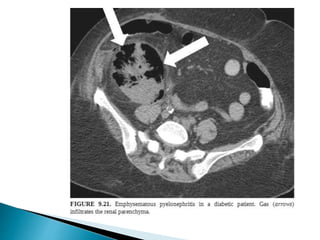

 Graft recipient >>> donor…

 Incidence and severity rely on

1. dose of immunotherapy

2. DM

3. Co-existant graft dysfunction.

 Organisms:- Gram negative pathogens/CMV/HSV.